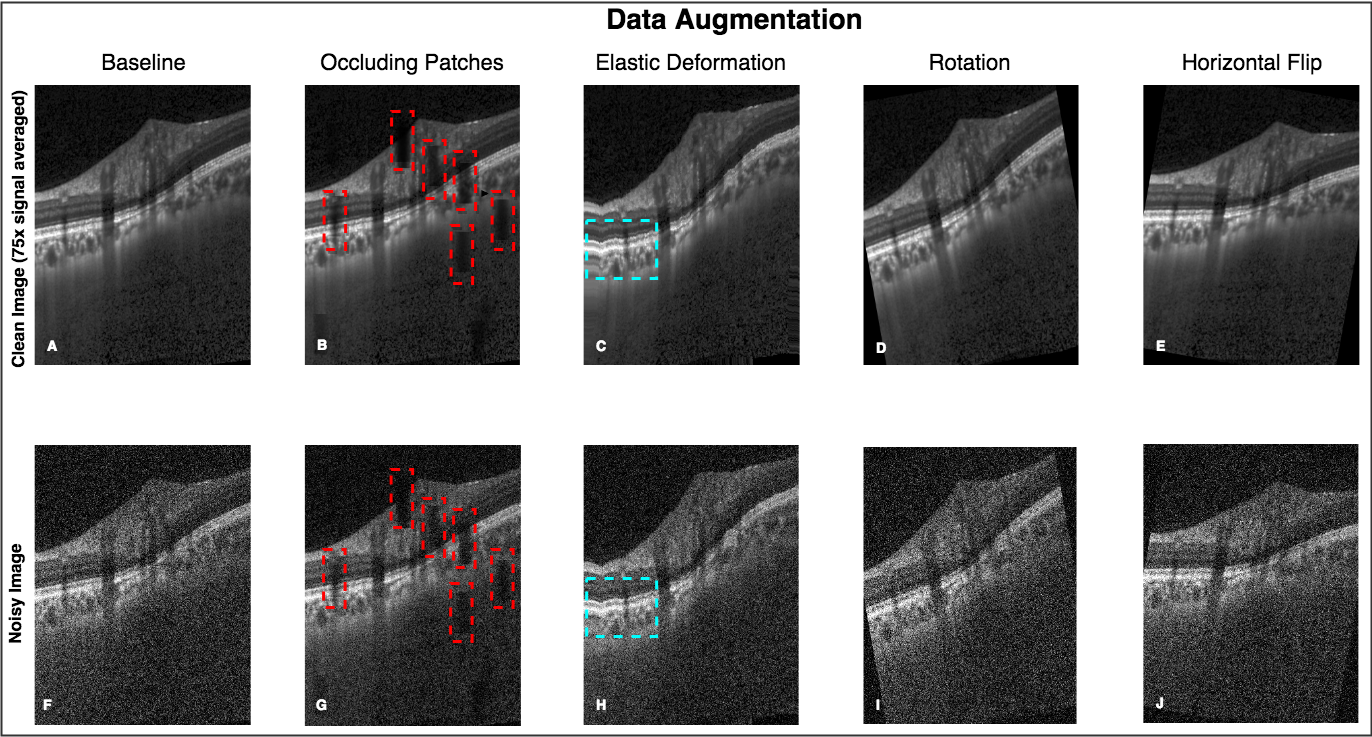

From the dataset of 3,880 B-scans, 2,328 of them (from both eyes of 12 subjects) were used as a part of the training dataset. The training set consisted of ‘clean’ B-scans and their corresponding ‘noisy’ versions. The ‘clean’ B-scans were simply the multi-frame (75x signal averaging) B-scans. The ‘noisy’ B-scans were generated by adding Gaussian noise ( and ) to the respective ‘clean’ B-scans (Figure 2).

2.7 Data Augmentation

An exhaustive offline data augmentation was done to circumvent the scarcity of training data. We used elastic deformations [75, 63], rotations (clockwise and anti-clockwise; ), occluding patches [63], and horizontal flipping for both ‘clean’ and ‘noisy’ B-scans. Briefly, elastic deformations were used to produce the combined effects of shearing and stretching in an attempt to make the network invariant to atypical morphologies (as seen in glaucoma [76]). Ten occluding patches of size 60 x 20 pixels were added at random locations to non-linearly reduce (pixel intensities multiplied by a random factor between 0.2 and 0.8) the visibility of the ONH tissues. This was done to make the network invariant to blood vessel shadows that are common in OCT B-scans [77]. Note that a full description of our data augmentation approach can be found in our previous paper [63].

Using data augmentation, we were able to generate a total of 23,280 ‘clean’ and 23,280 corresponding ‘noisy’ B-scans that were added to the training dataset. An example of data augmentation performed on a single ‘clean’ and corresponding ‘noisy’ B-scan is shown in (Figure 2).